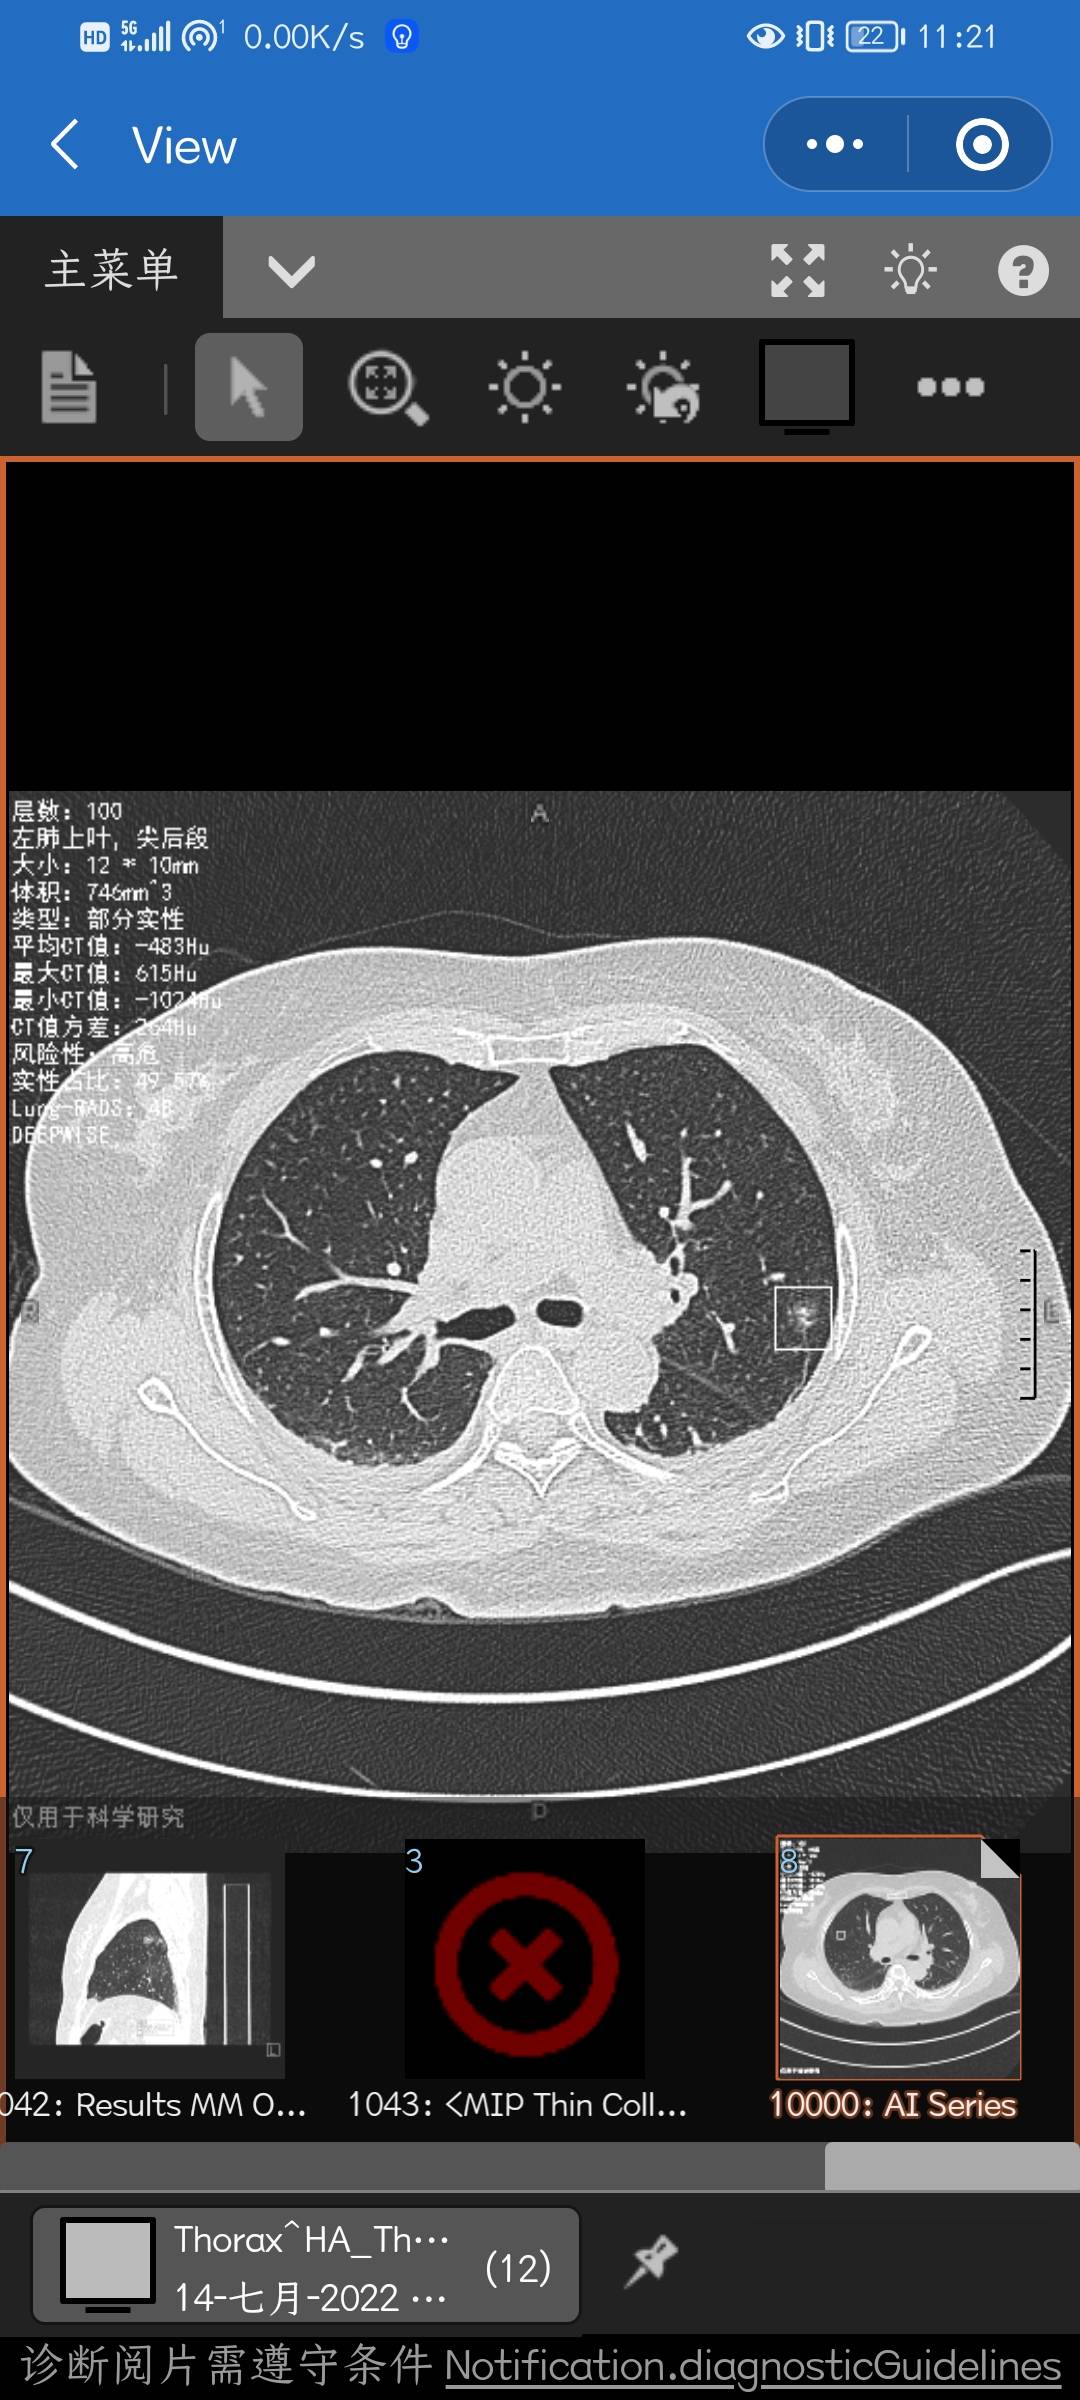

医生说是T1bN0M0,贴壁50%+腺泡30%+实性10%+乳头10%,KI-67(8%),恳请大家看看帮忙参考下,要不要后续辅助治疗?图片